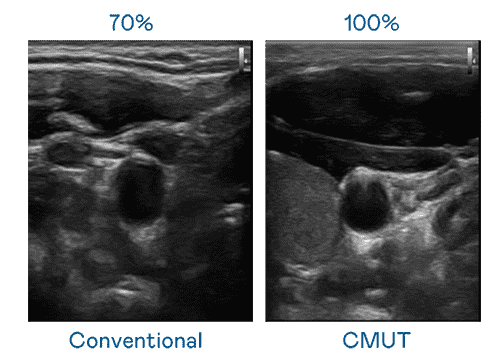

CMUT 技术是一种用电容式微机电元件来产生超音波讯号的技术。。与传统 PZT 压电式技术相比,,,CMUT 频宽增加 30%,,,更宽频的超音波讯号让影像解析度大幅提升,,是实现高影像品质医疗超音波扫描、、、、促进精准医疗发展的关键技术。。。

大频宽带来超清晰影像

超音波影像的解析度高低,,,首先取决于探头能发出的讯号频宽。。。传奇国际 CMUT 可提供高清晰的超音波讯号,,,,提供高频宽、、高灵敏度、、影像纹理细节更高的超音波影像,,协助医护人员缩短影像判读时间及利用精准的医疗影像进行诊断。。